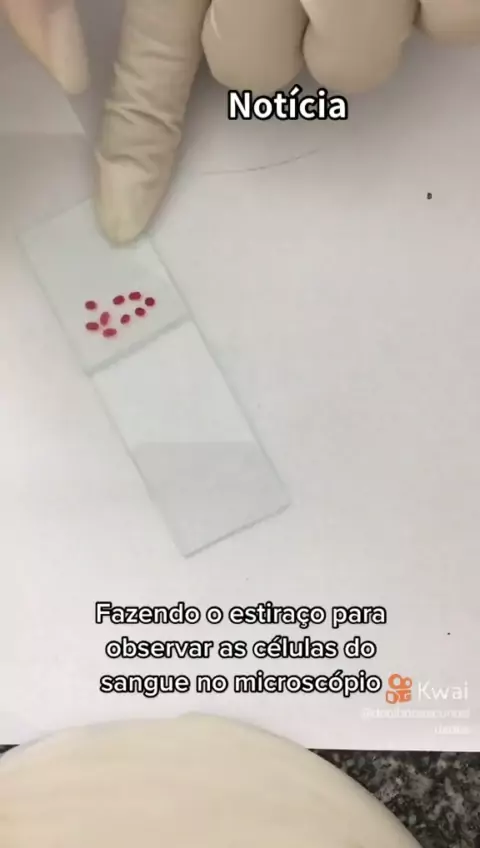

Fique por dentro... #necropsiaeeu #biomedicina #unicesumar #estudante #medicina

Curiosidades Necropsia. Fique por dentro. #necropsiaeeu #necropsia #estudo #curiosidade #brasil

Fique por dentro... #necropsiaeeu #biomedicina #unicesumar #estudante #medicina